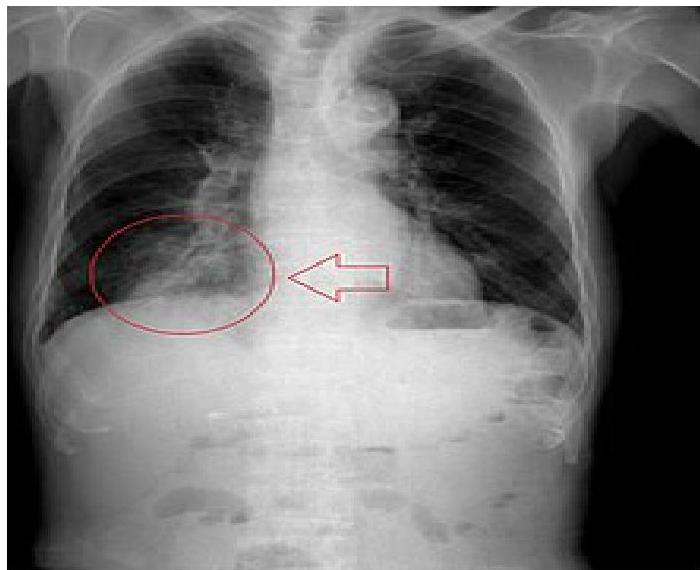

- Bronchial FBA Findings in chest x-ray:

- Hyperinflated lung

- Atelectasis

- Mediastinal shift

- Pneumonia

- Plain Film: Air trapping, obstructive emphysema, mediastinal shift